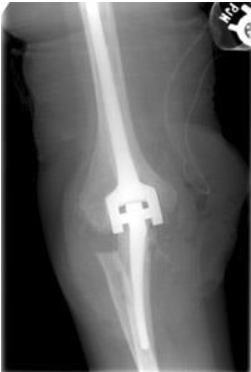

arthritis-xray

X-ray of a patient who underwent elbow joint replacement. If the joint surface has worn away completely, it is unlikely that anything other than a joint replacement would bring about relief. There are several different types of elbow joint replacement available.

In appropriately selected patients, the improvement in pain and function after a joint replacement can be dramatic.